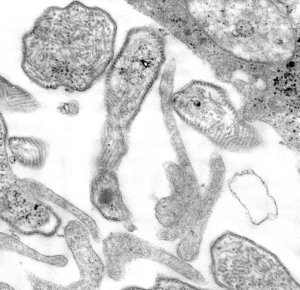

Mumps is a contagious disease caused by a virus. Mumps typically starts with a few days of fever, headache, muscle aches, tiredness and loss of appetite, followed by swollen salivary glands. Mumps can occasionally cause complications, including inflammation of the testicles or ovaries, meningitis or encephalitis. Most people with mumps recover completely in a few weeks.